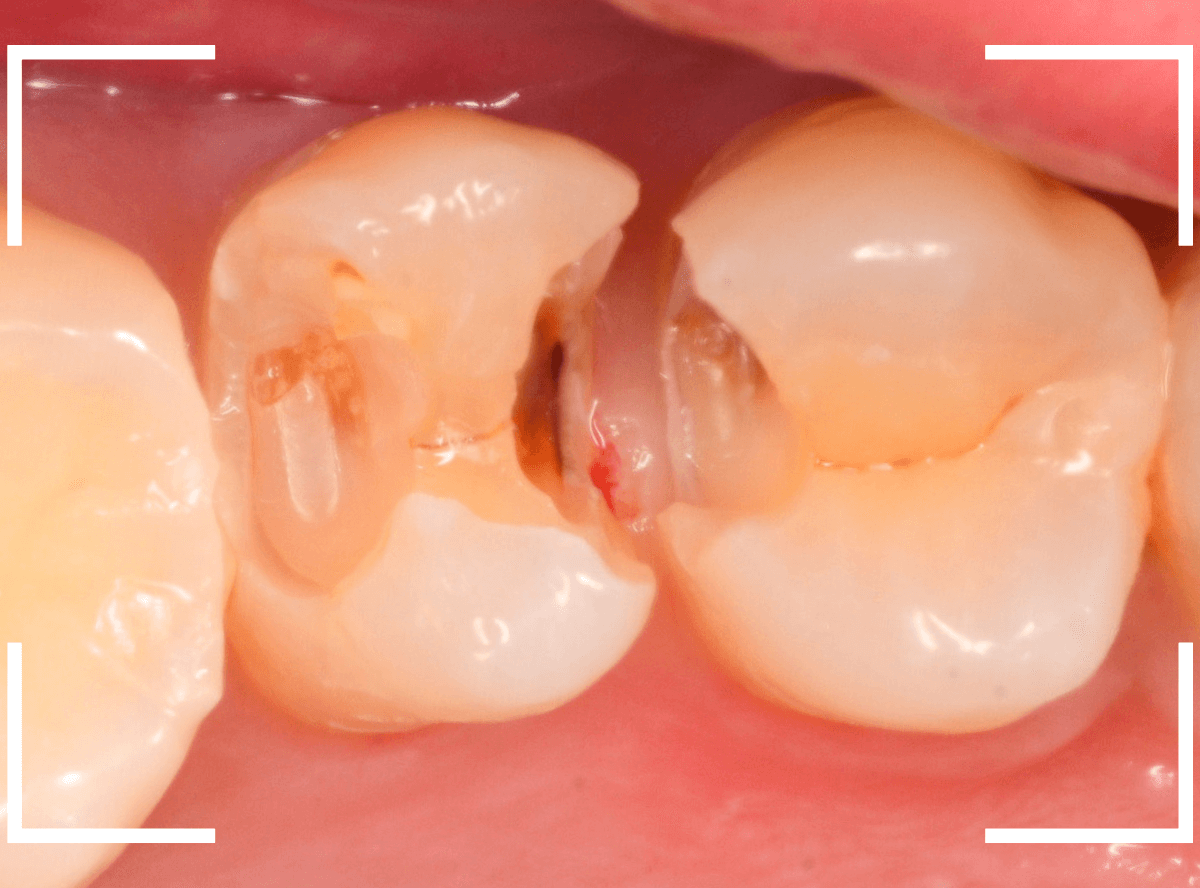

金属を外したところです。

写真では写ってしませんが、この奥に虫歯があります。

全ての虫歯を除去したところです。

抜歯した後ろのおやしらずは、元々虫歯の治療がしてありましたが、その際に抜歯しておいた方が良かったのではないかな、と思いました。